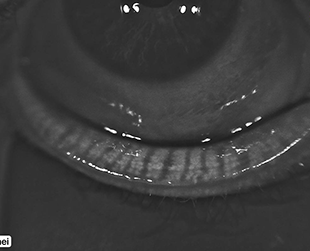

Corneal Topography

for keratoconus and contact lens fitting

Meibography

for dry eye diagnosis